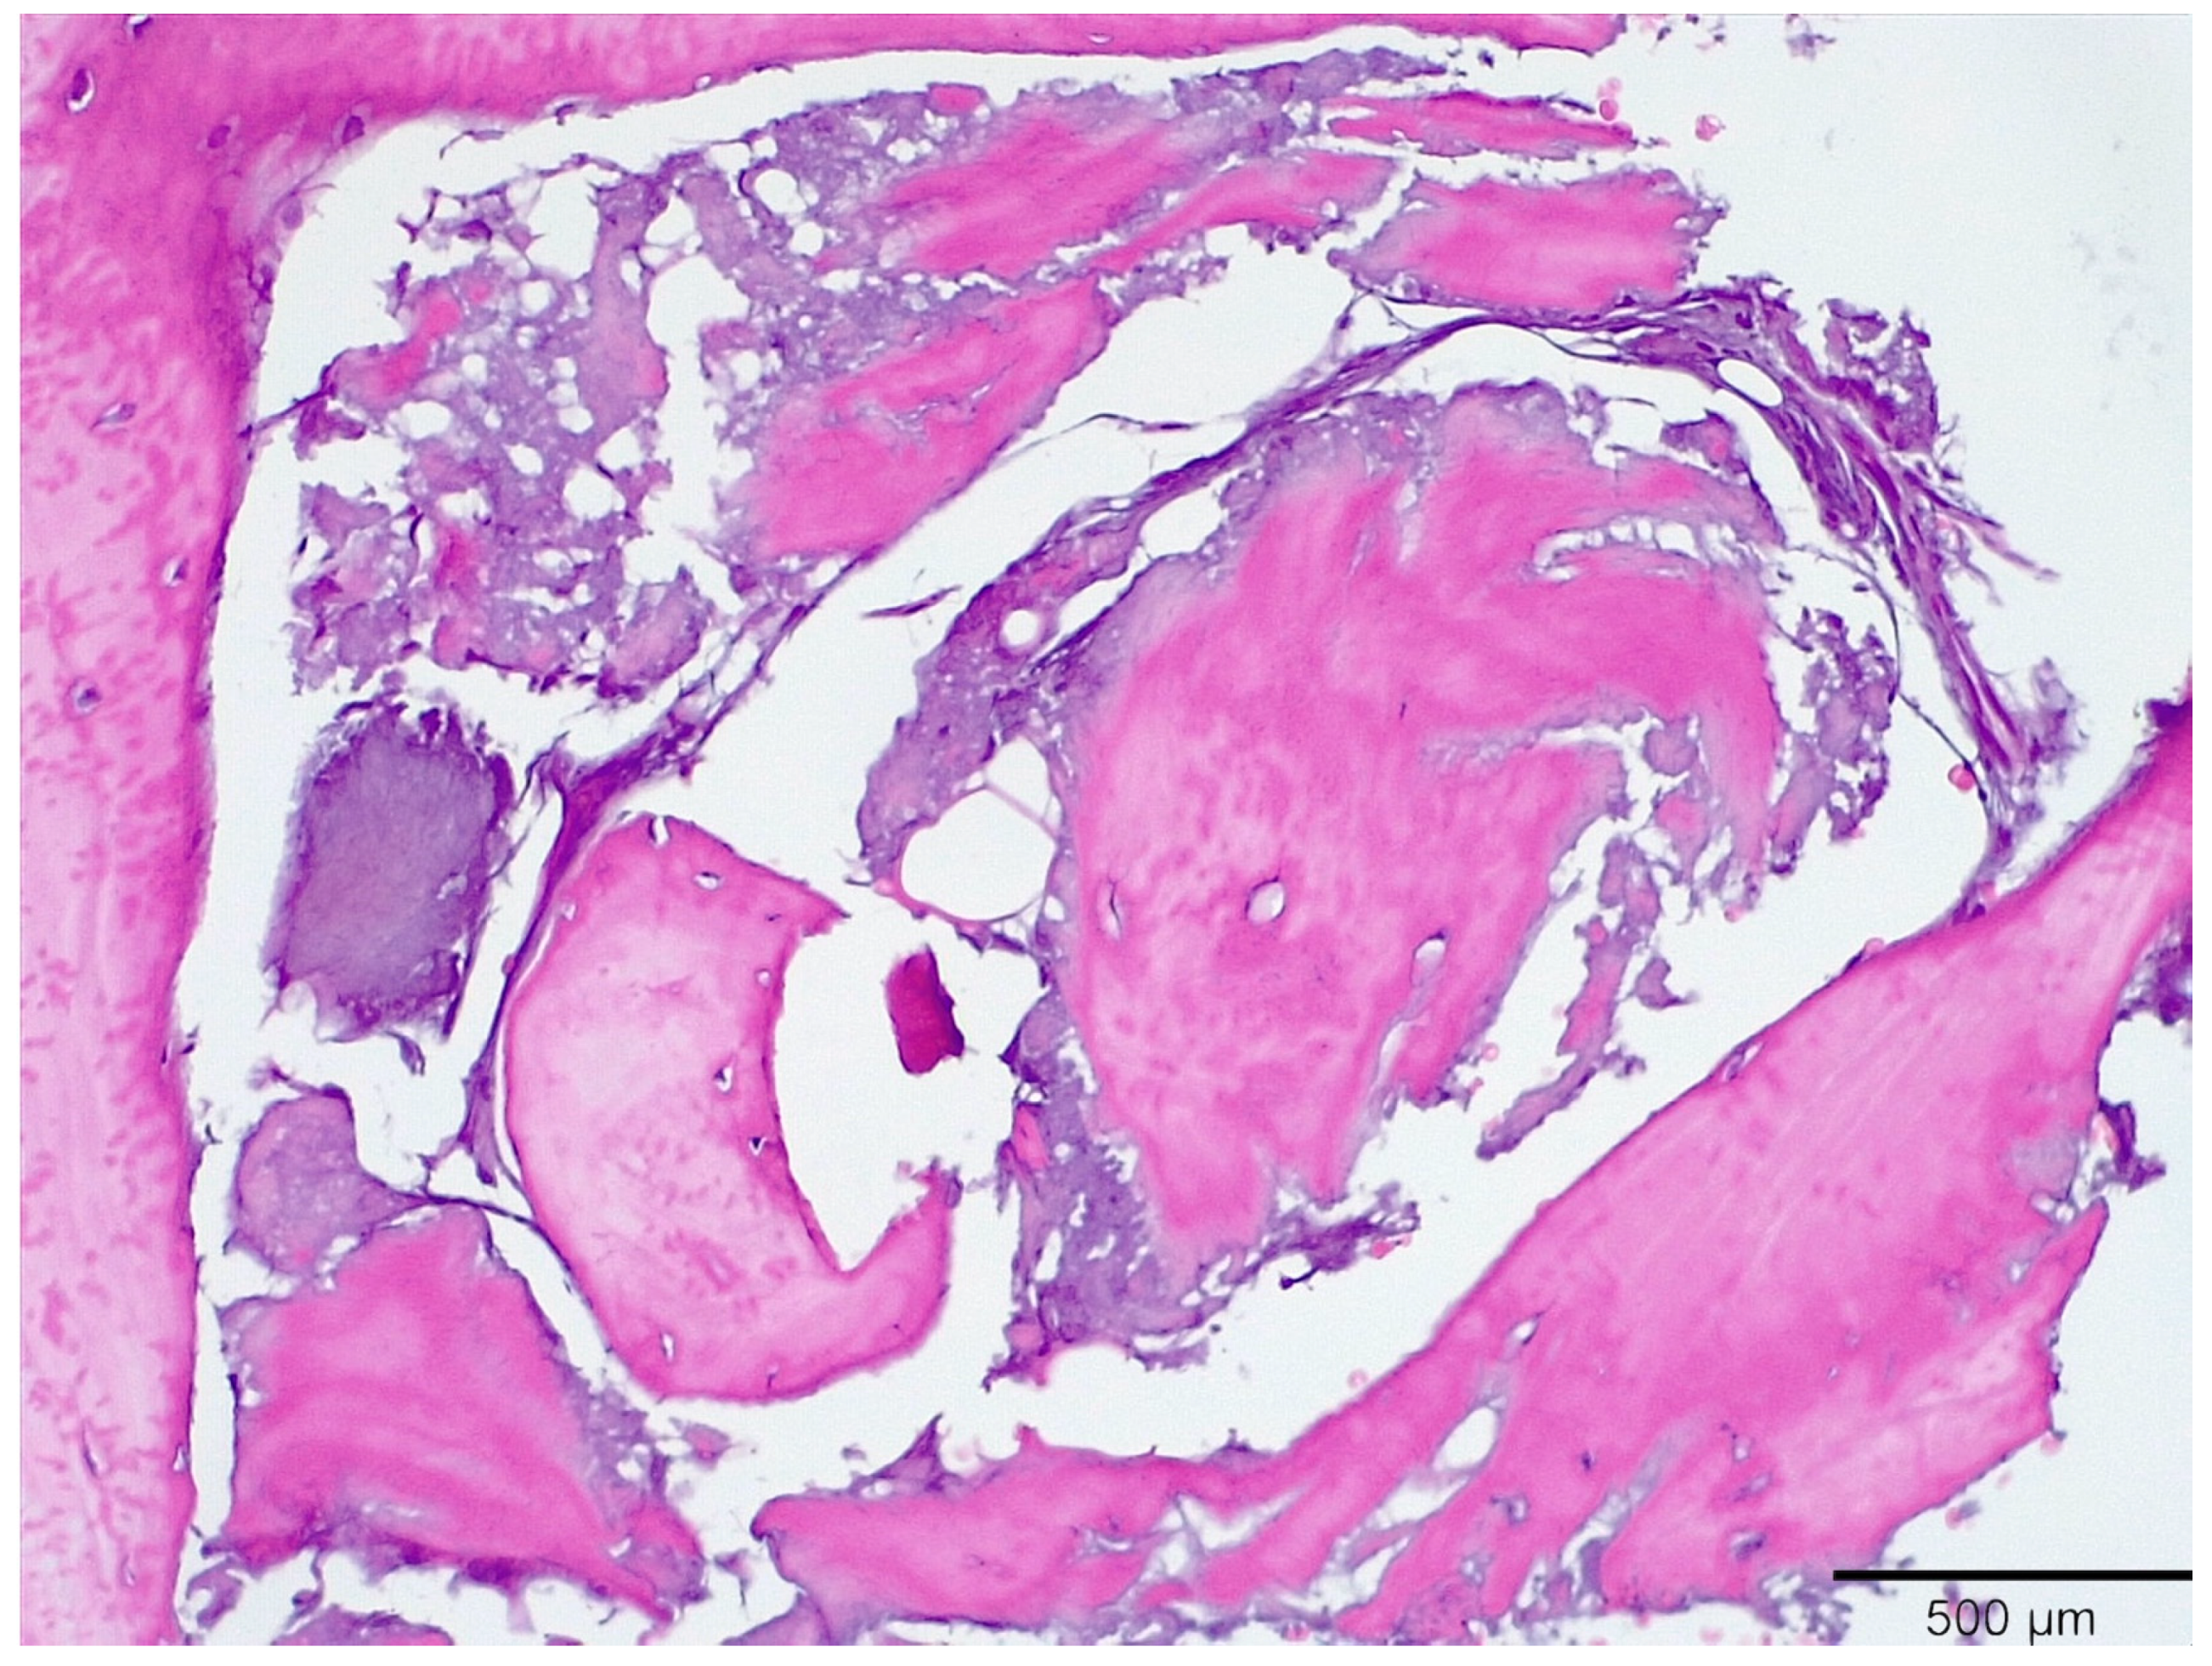

3.1. Histological Analysis Showed Signs of New Bone Formation at 60 Days

3.2. Histologic Data Obtained after Samples Analysis at 24 Months of Evaluation